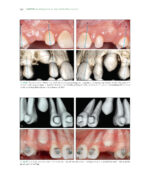

The Ortho-Perio Patient: Clinical Evidence and Therapeutic Guidelines 2019

کتاب افست ” The Ortho-Perio Patient: Clinical Evidence and Therapeutic Guidelines 2019 ” ویرایش اول